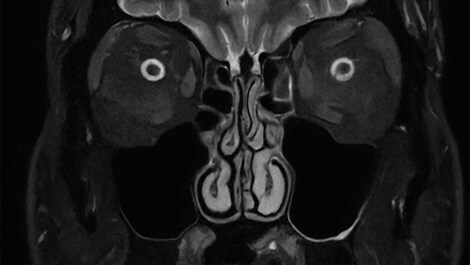

Mit der neuesten Version der Bedienoberfläche – MR Workspace R12⁵ – stellt Philips einen „Zero-Click“-Workflow vor, der den gesamten Bildgebungsprozess von der Auswahl der Systemparameter bis zur Berichterstellung nahtlos steuert. Durch die Reduzierung manueller Eingriffe trägt MR Workspace R12 dazu bei, den Patientendurchsatz zu erhöhen und Wartezeiten zu reduzieren, wodurch der steigenden Nachfrage nach schnellerer und präziserer Bildgebung der Radiologieabteilungen Rechnung getragen wird. Eine der wichtigsten Innovationen von MR Workspace R12 ist die KI-gestützte SmartExam-Funktion, die 80 % der MR-Verfahren automatisiert⁶, die Anzahl der Mausklicks in den Arbeitsabläufen minimiert und Bildgebungs-Workflows standardisiert. Die nun vorgestellte SmartSpeed Precise¹-Technologie steigert die Produktivität weiter und ermöglicht es, Scans bis zu dreimal schneller durchzuführen⁷, wodurch die Scanzeiten bei gleichbleibender Bildqualität erheblich verkürzt werden. Das Herzstück von SmartSpeed Precise ist die Anwendung zweier KI-Modelle in der Bilddatenrekonstruktion⁸, die eine 80-prozentige Steigerung der Bildschärfe⁹ ermöglicht und die diagnostische Genauigkeit weiter verbessert. Diese leistungsstarke Kombination aus Geschwindigkeit und Präzision ermöglicht es Radiologinnen und Radiologen, Anomalien differenzierter und klarer zu erkennen, was letztlich zu besseren Behandlungsergebnissen für die Patientinnen und Patienten führt. Zu den weiteren bahnbrechenden Innovationen gehört Smart Reading⁴, die erste und branchenführende Lösung, die eine cloudbasierte, KI-gestützte quantitative Berichterstattung integriert. Smart Reading nutzt modernste KI-Plattformen wie icobrain (icometrix) für die Neurologie – einschließlich automatischer Erkennung der mit Alzheimer assoziierten Anomalien – und QP-Prostate (Quibim) für die fortgeschrittene Prostatakrebsdiagnostik. Durch die Bereitstellung hochzuverlässiger Diagnosen sorgen diese KI-Lösungen ohne Mausklick für eine optimierte, datengestützte Entscheidungsfindung für Ärztinnen und Ärzte. Mit MR Workspace R12, SmartSpeed Precise und Smart Reading erweitert Philips die Grenzen der KI in der MRT weiter und treibt die Effizienz und Genauigkeit in der diagnostischen Bildgebung voran, während es gleichzeitig den Weg für die Zukunft des autonomen MR-Scannings ebnet.